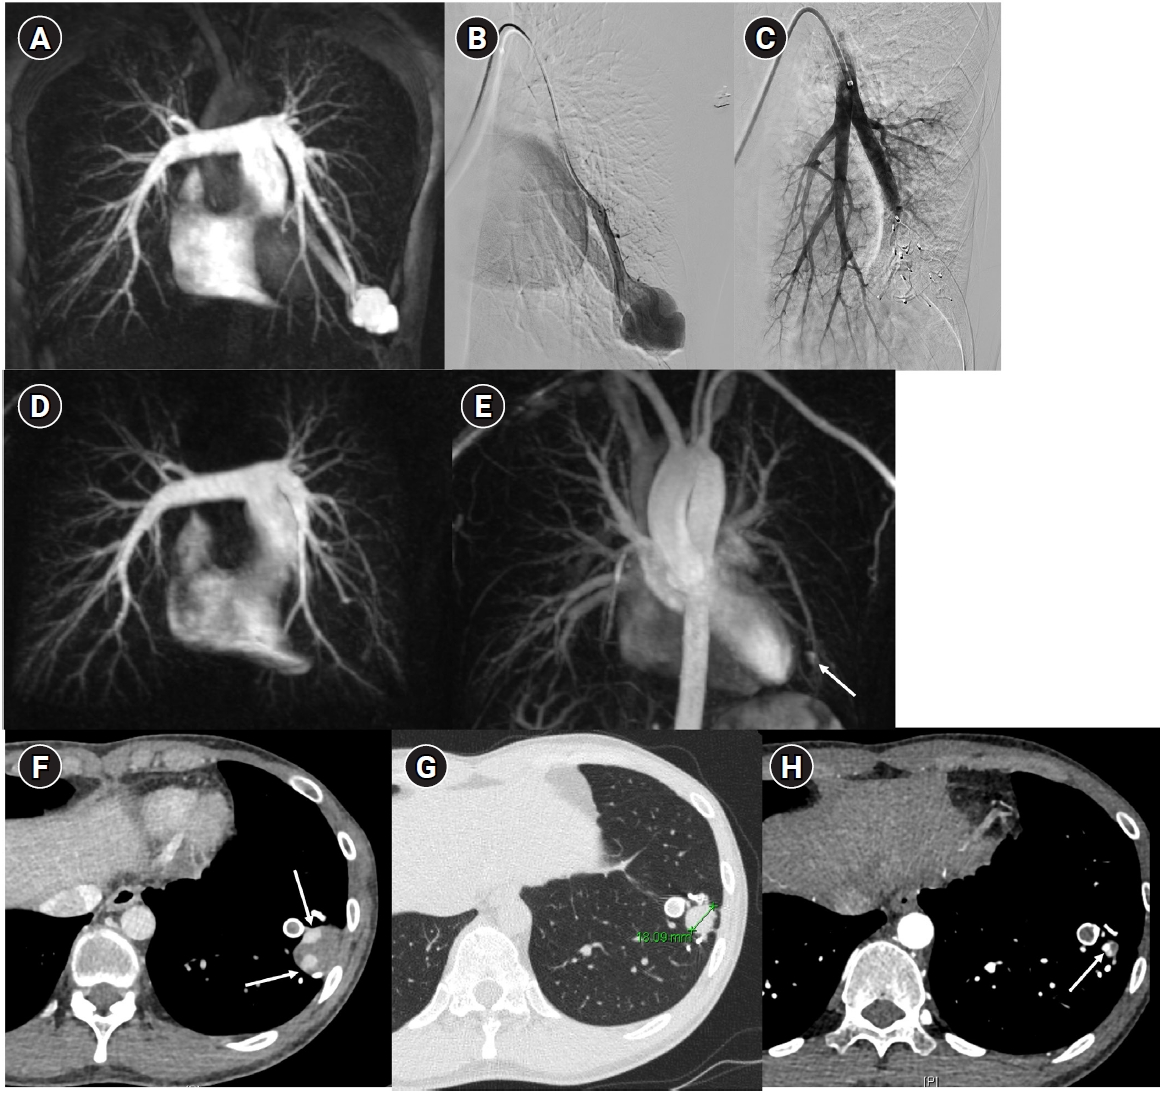

Fig. 6.

Time-resolved magnetic resonance angiography (TR-MRA) and procedural images of a pulmonary arteriovenous malformation showing recanalization. (A) In the TR-MRA performed before the procedure, a venous sac (arrow) is observed concurrently with the feeding artery (dashed arrows). (B) Recanalization was confirmed in the selective angiography. (C) Utilizing additional coils and an 8 mm Amplatzer vascular plug type IV (AVP 4) (arrow), the feeding artery embolization was carried out. (D) On the 6-month follow-up TR-MRA, the feeding artery is no longer visible, and the venous sac is also not observed.

kjir-2026-00010f6.jpg

Long-term follow-up after treating PAVMs is needed to detect newly developed PAVMs and to identify persistence or recurrent flow [10,11]. Treatment failure in PAVMs can be classified as recanalization and reperfusion. Recanalization refers to the reopening of blood flow through spaces between the previously placed embolic material (Fig. 6). Reperfusion, on the other hand, occurs when blood flow from an adjacent pulmonary artery reopens the previously embolized distal vein or venous sac (Fig. 7) [32]. As the primary follow-up modality, CT is recommended, but there are currently no specific guidelines on whether or not to use contrast enhancement [33]. It is recommended to perform an initial evaluation by CT about 6 months after PAVM embolization, and then follow-up with CT every 3–5 years thereafter (Fig. 8). In CT follow-up, the evaluation is based on the reduction rate of the venous sac or the draining vein, and the traditional criterion is that there should be at least a 70% reduction in the size of the venous sac or draining vein [34,35]. In recent studies, there have been opinions that this 70% size reduction criterion is too strict. In response, some research using angiographic-confirmed cases or time-resolved magnetic resonance angiography (TR-MRA) has proposed a 50%–60% guideline [36,37]. When using CT, repeated radiation exposure and metal artifacts from the coils can be problematic. By using metal artifact reduction techniques, it is possible to obtain clear images of the surrounding parenchyma, and this also helps in assessing parameters like the draining vein diameter reduction rate (Fig. 9) [38]. Furthermore, low-dose CT protocols may help reduce cumulative radiation exposure during repeated follow-up imaging.

In parallel, increasing attention has been directed toward the role of dynamic imaging modalities, particularly TR-MRA [39-42]. Reperfusion can be confirmed if the draining vein is observed simultaneously with the pulmonary artery on TR-MRA. Because TR-MRA can clearly distinguish between the pulmonary arterial and pulmonary venous phases, and because it is less affected by coil artifacts, it allows for a more reliable differentiation between residual arteriovenous malformation and residual sac filling caused by normal pulmonary vein drainage (Fig. 10) [41].